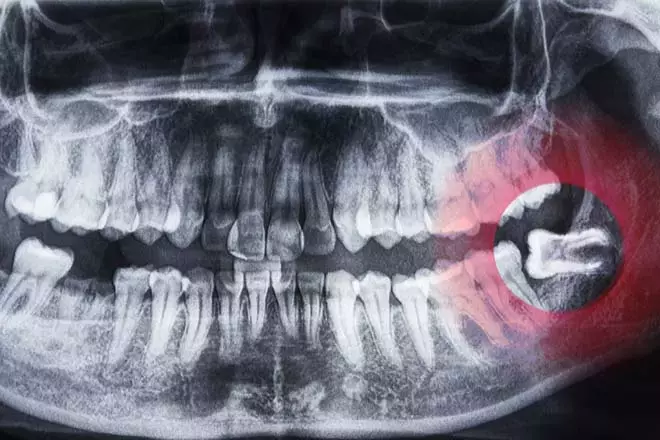

2. 20’lik dişler

Atalarımızın sert ve çiğ yiyecekleri öğütmesine yardımcı olan 20’lik dişler, günümüzün pişmiş ve işlenmiş gıdalarıyla artık işlevsiz. İngiltere’de yetişkinlerin yaklaşık yüzde 20’si en az bir 20’lik dişini çektirmiş durumda. Uzmanlar, gelecek nesillerde bu dişlerin tamamen kaybolabileceğini belirtiyor.